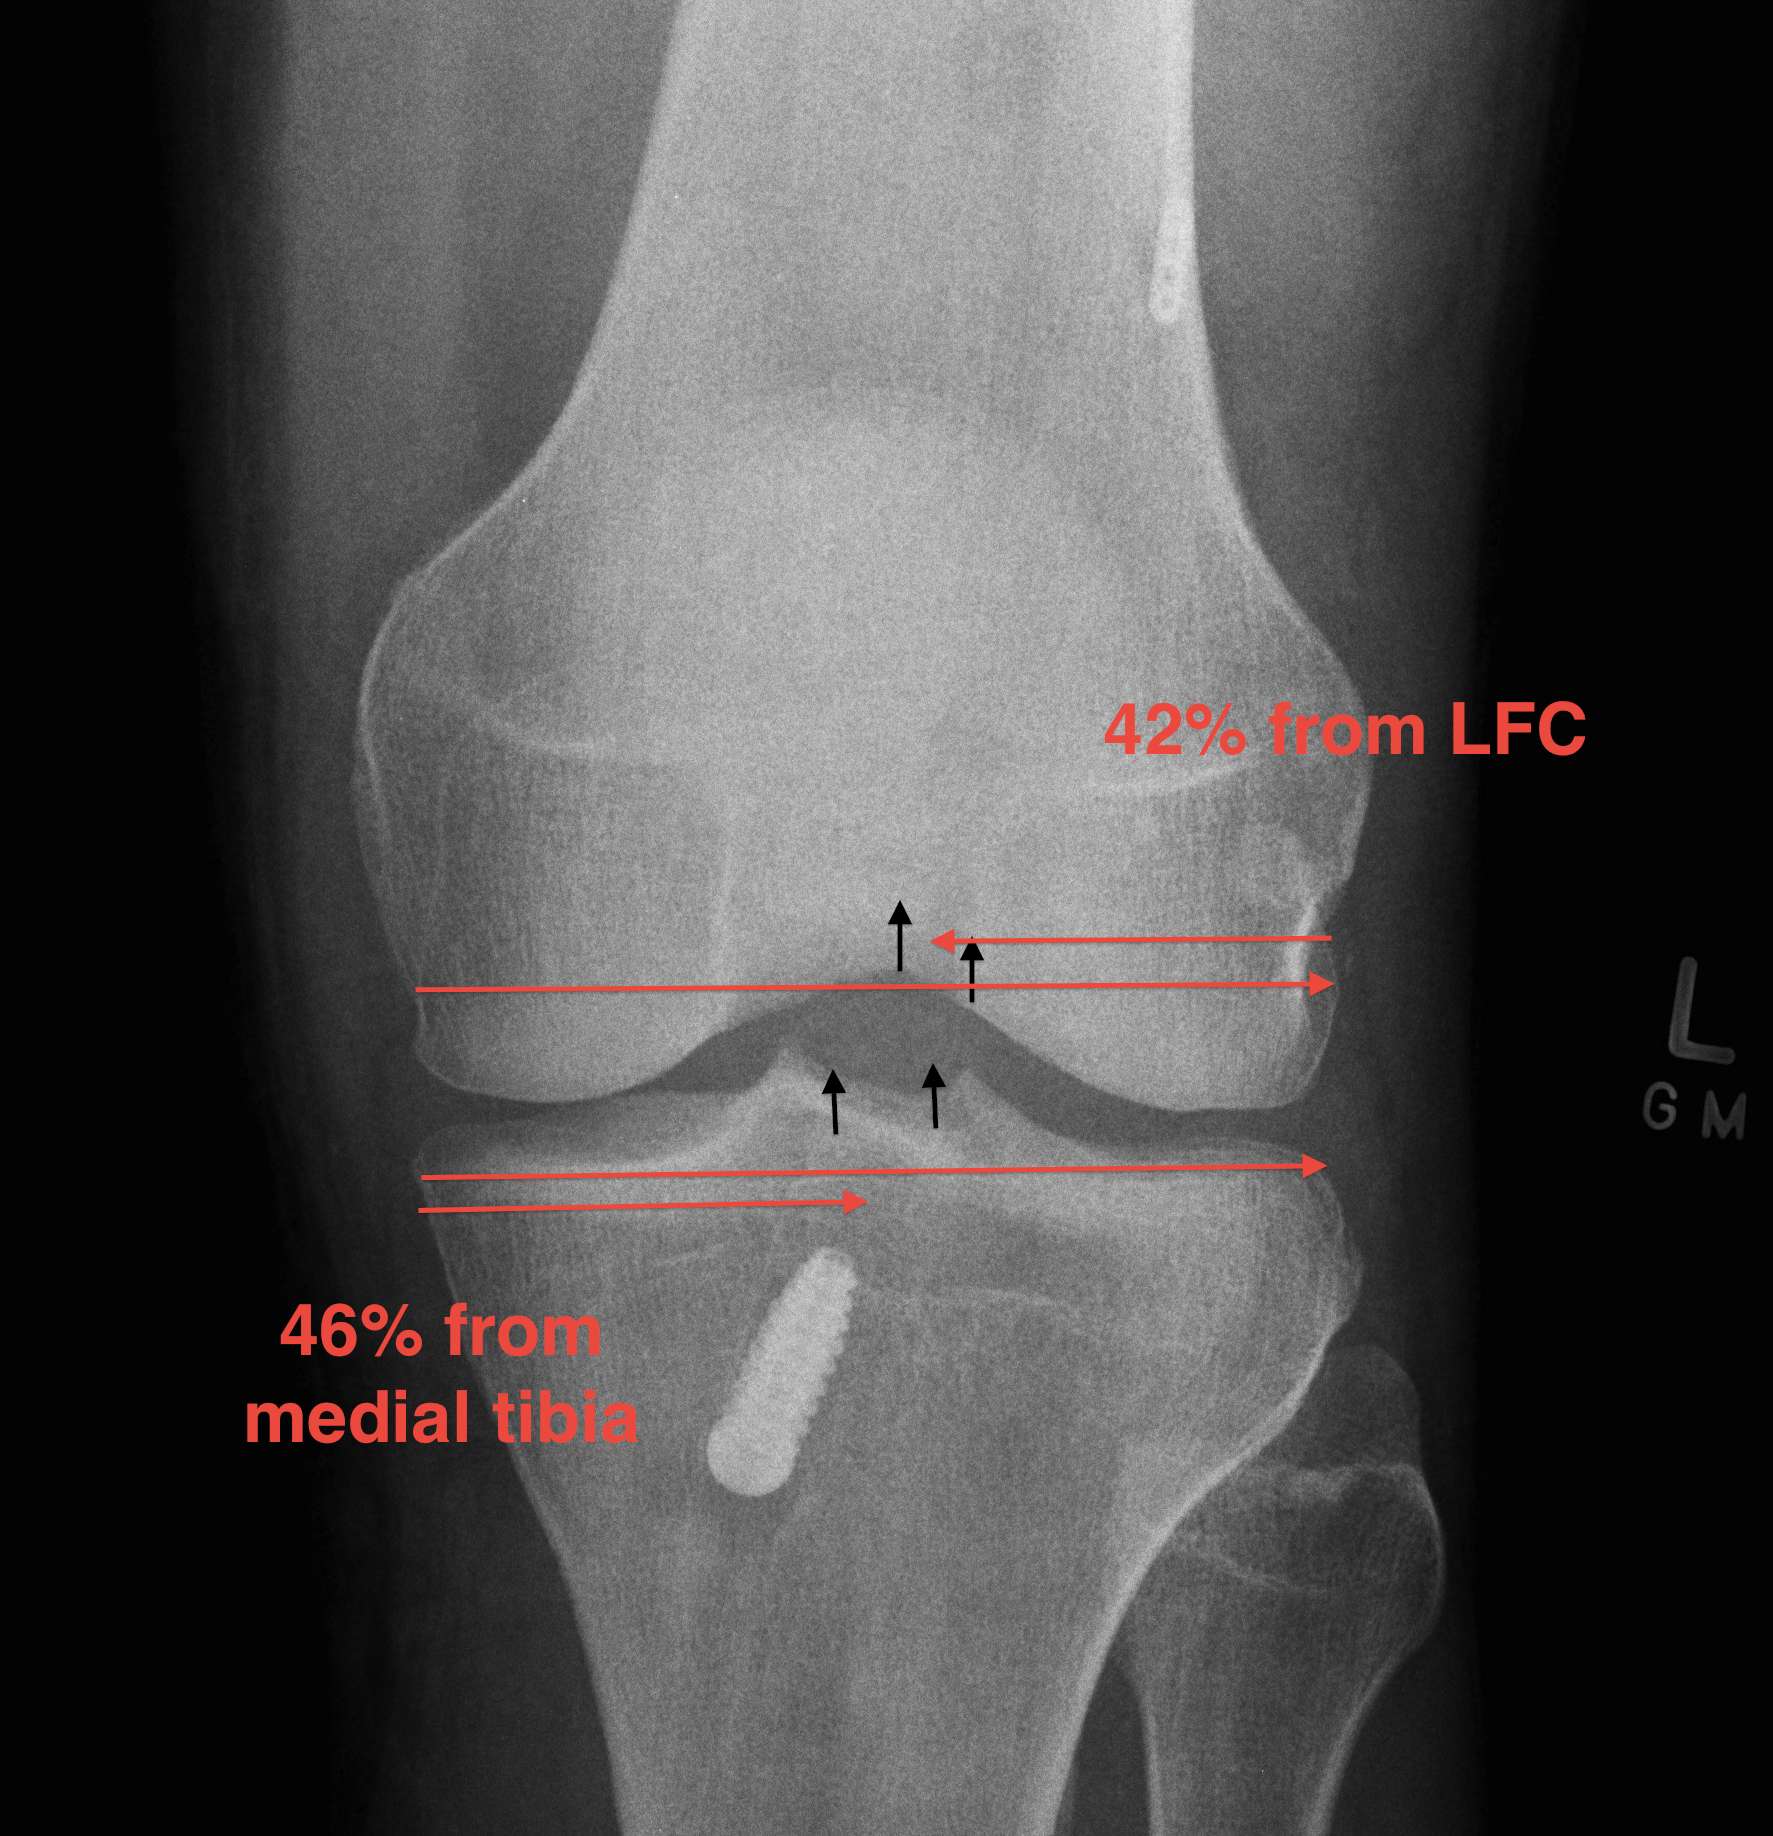

AP Xray

1. Medial tibial tunnel placement

- 46% (towards medial)

2. Lateral femoral tunnel placement

- 42% from lateral LFC

3. Graft inclination

- 19o

11% rupture rate over 7 years

- associated with posterior tibial tunnel placement

Good rotational stability

- 19o inclination in coronal plane

- avoid too vertical orientation